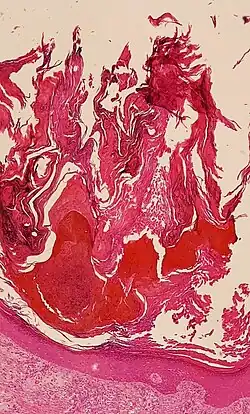

An inability to correctly maintain the skin barrier function due to the dysregulation of epidermal components can lead to skin disorders. For example, a failure to modulate the activity of kallikreins via the disruption of the protease inhibitor LEKTI causes the debilitating disorder Netherton syndrome.[11]

Hyperkeratosis is an increased thickness of the stratum corneum, and is an unspecific finding, seen in many skin conditions.